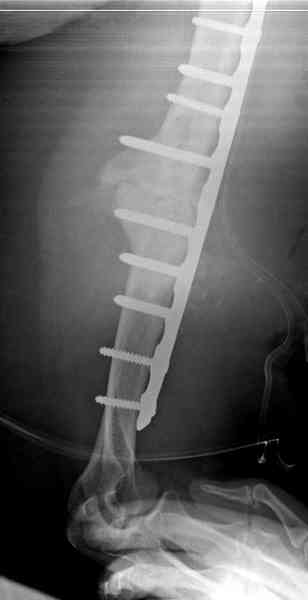

Когда разбирался случай на сайте, и у нас была больная с похожей

патологией, ложный сустав после поперечного перелома, леченного год

назад где-то и кем-то в другом месте.

Первичную пластину убрали недели 6 назад из переднего оригинального

доступа, и из-за подозрительности тканей вокруг пластины, решили

провести реконструкцию поэтапно.